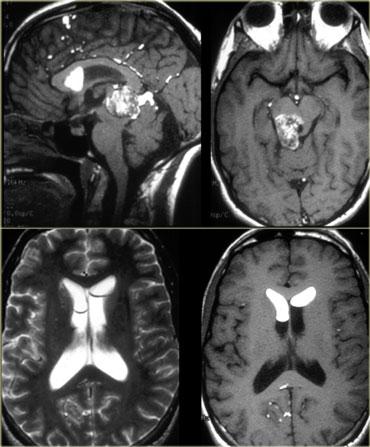

Hình bên trái là một số ví dụ về các khối u có cường độ tín hiệu thấp trên chuỗi xung T2W.

- Di căn u hắc tố có tín hiệu thấp trên chuỗi xung T2W do melanin.

- GBM có thể có tín hiệu thấp trên chuỗi xung T2W vì đôi khi chúng có tỷ lệ nhân-bào tương cao. Tuy nhiên, hầu hết GBM tăng tín hiệu trên chuỗi xung T2W.

- PNET thường có tỷ lệ nhân-bào tương cao. PNET chủ yếu nằm ở vùng não thất IV, nhưng một vị trí khác ít gặp hơn là vùng tuyến tùng.

- Di căn từ ung thư nhầy (mucinous metastases) có thể có tín hiệu thấp trên chuỗi xung T2W vì chúng thường chứa vôi hóa.

- U màng não (meningioma) thường có tín hiệu trung gian.

Chúng có thể có tín hiệu cao trên chuỗi xung T2W nếu chứa nhiều nước.

Chúng có thể có tín hiệu thấp trên chuỗi xung T2W nếu rất đặc và tăng sinh tế bào cao hoặc khi chứa vôi hóa.